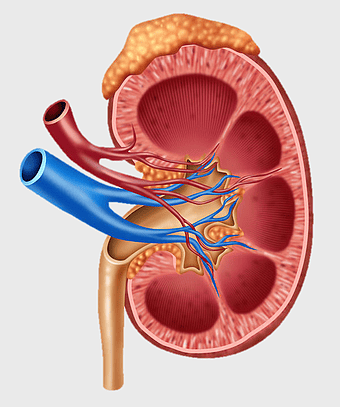

- kidney and liver diagram

kidney anatomy diagram, human kidney structure, retroperitoneal space illustration, blood vessels in kidneys, renal system visualization, medical kidney illustration, kidney cross-section analysis -

chronic kidney disease illustration, nephron structure diagram, kidney transplant medical image, excretory system anatomy, renal blood flow visualization, human kidney cross-section, medical education graphics -

kidney anatomy diagram, human kidney structure, adrenal gland and kidney, kidney stone illustration, renal system diagram, urinary system anatomy, kidney blood vessels -